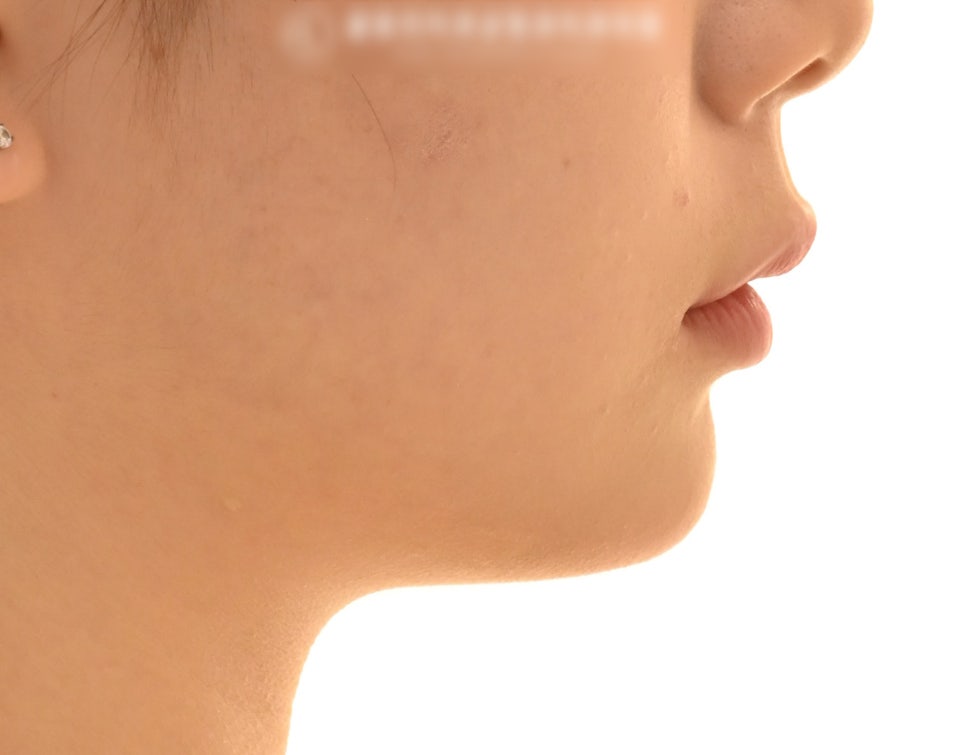

동시에, 이 환자의 경우

입술의 긴장감도 있었기에

이러한 부분들도 같이 고려를 하여

돌출입 교정을 진행하기로 했습니다.

돌출된 입 또한 자연스럽게 들어가

후방으로 잘 견인된 모습을 보이는데요.

발치를 통해 배열 및 돌출감 개선으로

처음 초진 시 수립했던 계획이 잘 완료된 것을

알 수 있었습니다.